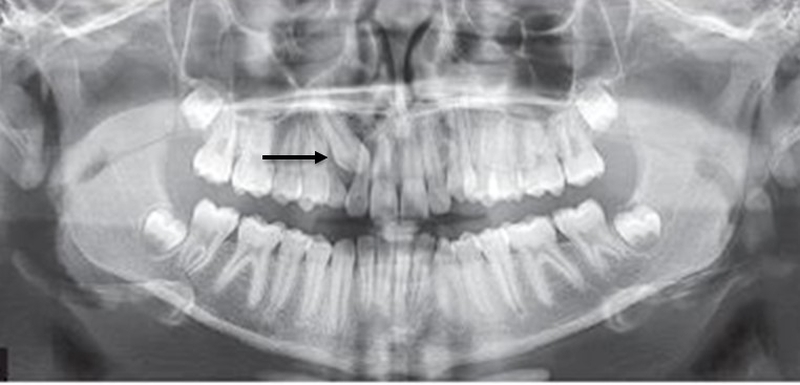

Răng mọc ngầm là tình trạng răng mọc sâu bên trong xương hàm hoặc nằm dưới nướu nhưng không trồi lên được. Chính vì vậy mà rất khó để có thể dấu hiệu răng mọc ngầm. Bạn có thể nhận biết được một số dấu hiệu lâm sàng nhưng để chắc chắn thì cần phải chụp X-quang răng để biết có răng mọc ngầm hay không, răng ngầm nằm ở vị trí nào.

Để xác định chính xác là bạn có đang gặp tình trạng răng mọc ngầm hay không không thể chỉ dựa vào những dấu hiệu răng mọc ngầm trên. Nếu bạn nhận thấy bản thân đang gặp phải nhưng vấn đề trên thì nên tiến hành chụp X quang răng tại phòng khám nha khoa mới đánh giá rõ được.